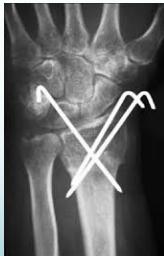

K-wire (Kirschner Wire)

- Indications:

- Fixation of Pediatric fractures

- Small bone fractures in adults

- Advantages:

- Easy to apply

- Easy to remove

- Disadvantages/Problems:

- Not stable alone

- Infection if end left outside skin